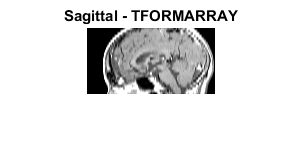

T0 = maketform('affine',[0 -2.5; 1 0; 0 0]); R2 = makeresampler({'cubic','nearest'},'fill'); M3 = imtransform(M2,T0,R2); figure; imshow(M3,map); title('Sagittal - IMTRANSFORM');

T1 = maketform('affine',[-2.5 0; 0 1; 68.5 0]); inverseFcn = @(X,t) [X repmat(t.tdata,[size(X,1) 1])]; T2 = maketform('custom',3,2,[],inverseFcn,64); Tc = maketform('composite',T1,T2); R3 = makeresampler({'cubic','nearest','nearest'},'fill'); M4 = tformarray(D,Tc,R3,[4 1 2],[1 2],[66 128],[],0); figure; imshow(M4,map); title('Sagittal - TFORMARRAY');

figure, imshow(M3,map);

title('Sagittal - IMTRANSFORM')

figure, imshow(M4,map);

title('Sagittal - TFORMARRAY');